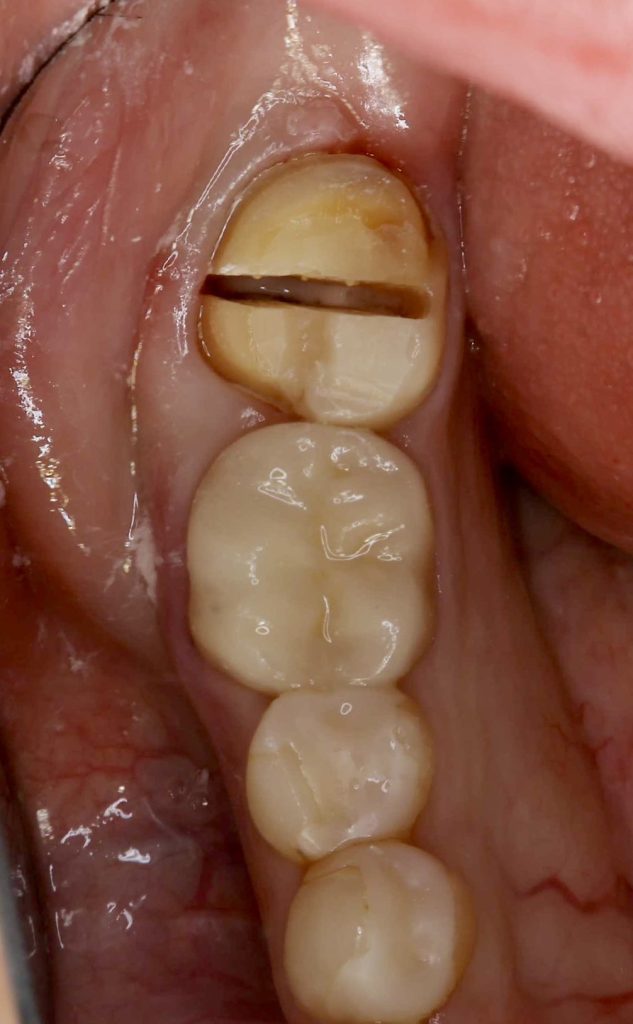

| 診断結果 | 右下7番歯根破折 |

| 治療内容 | 抜歯即時インプラント |

| 治療期間 | 8週間 |